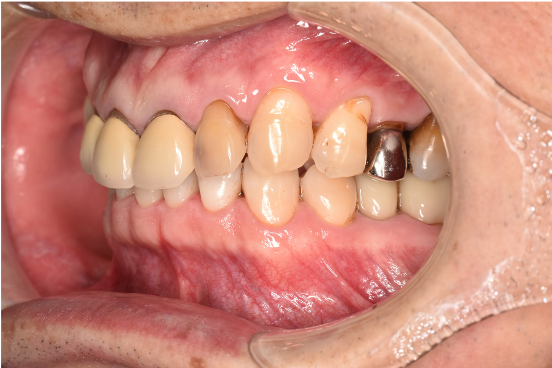

治療後

| 行ったご提案・治療内容 | 初診時に撮影したレントゲン、口腔内写真、歯周検査の結果を用いて、着色除去、歯周病治療の必要性をお伝えしました。 初診時は歯ブラシのお話しをさせていただき、セルフケアの方法について説明を行い、その後気にされてみえた着色除去、歯肉縁上歯石除去を行いましました。 歯肉の炎症がある程度落ち着いたところで、後日、再評価を行い歯周治療へ移行しました。 |

| 術後の経過・現在の様子 | 術後の経過は順調で、着色除去後、鏡でお口の中を確認をしていただいたところ、「とても綺麗になった!ご丁寧にありがとうございます」と仰っていただけました。 |